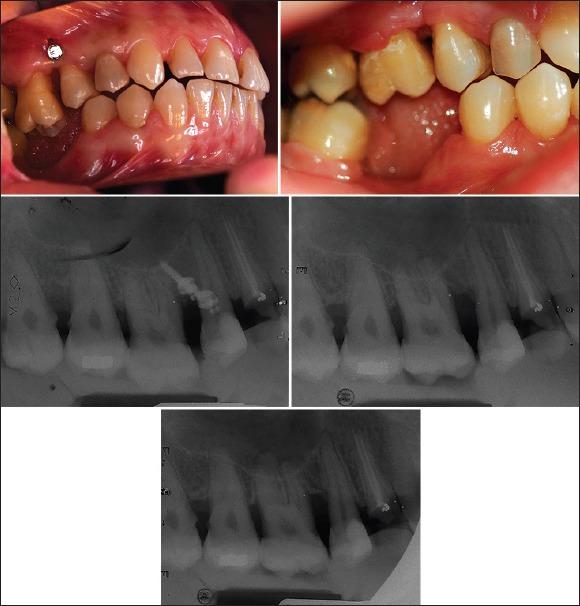

Ten female patients were enrolled in this study. Maxillary molar intrusion was achieved by inserting two miniscrews and a 17 × 25 titanium molybdenum alloy spring. Crestal height changes were evaluated at three intervals including: Baseline (T0), end of active treatment (T1) and 6 months after retention (T2). Other variables including probing depth, gingival recession, attachment level and bleeding on probing were evaluated by clinical measurements in the three above mentioned intervals. One-sample Kolmogrov-Smirnov test ascertained the normality of the data. For all patients, the changes in tooth position and crestal height were evaluated using one-sample t-test. (P < 0.05).

Supra-erupted molars were successfully intruded a mean of 2.1 ± 0.9 mm during active treatment (T0-T1). A mean bone resorption of 0.9 ± 0.9 mm in mesial crest and 1 ± 0.8 mm in distal crest had occurred in total treatment (T0-T2). A mean of 0.6 ± 1.4 mm bone was deposited on mesial crest during the retention period (T1-T2) following tooth relapse. On average, 0.8 ± 0.4 mm attachment gain was obtained. Gingival margin coronalized a mean of 0.8 ± 0.6 mm throughout the entire treatment. Probing depth showed no significant change during treatment.

Within the limitations of this study, these results suggest that not only periodontal status was not negatively affected by intrusion, but also there were signs of periodontal improvement including attachment gain and shortening of clinical crown height.